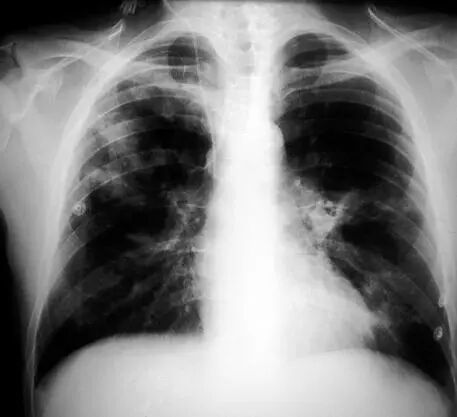

图1.1 细菌性肺炎。右上叶肺炎患者的放射影像。胸廓前后径增大,提示有慢性阻塞性肺疾病(COPD)。